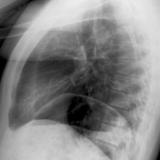

LUL Collapse Case 3 PA

Date: 02/19/2004

Views: 3336